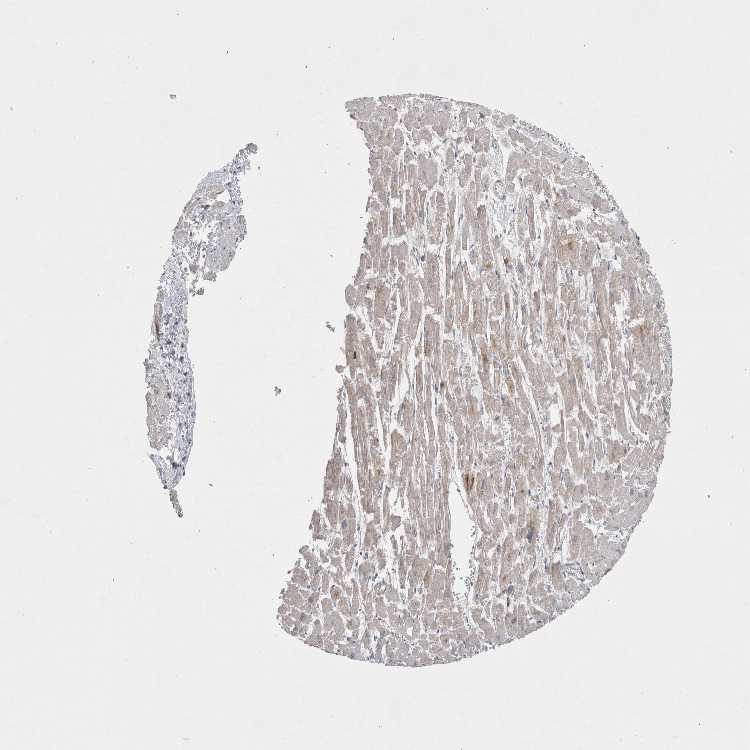

HEART MUSCLE - Antibody stainingi

Antibody staining in the annotated cell types in the current human tissue is reported as not detected, low, medium, or high, based on conventional immunohistochemistry profiling in selected tissues. This score is based on the combination of the staining intensity and fraction of stained cells.

Each image is clickable and will lead to virtual microscopy that enables deeper exploration of all samples and also displays staining intensity scores, fraction scores and subcellular localization as well as patient and tissue information for each sample.

Antibody HPA024704Antibody CAB032791

Cardiomyocytes Not detectedMedium